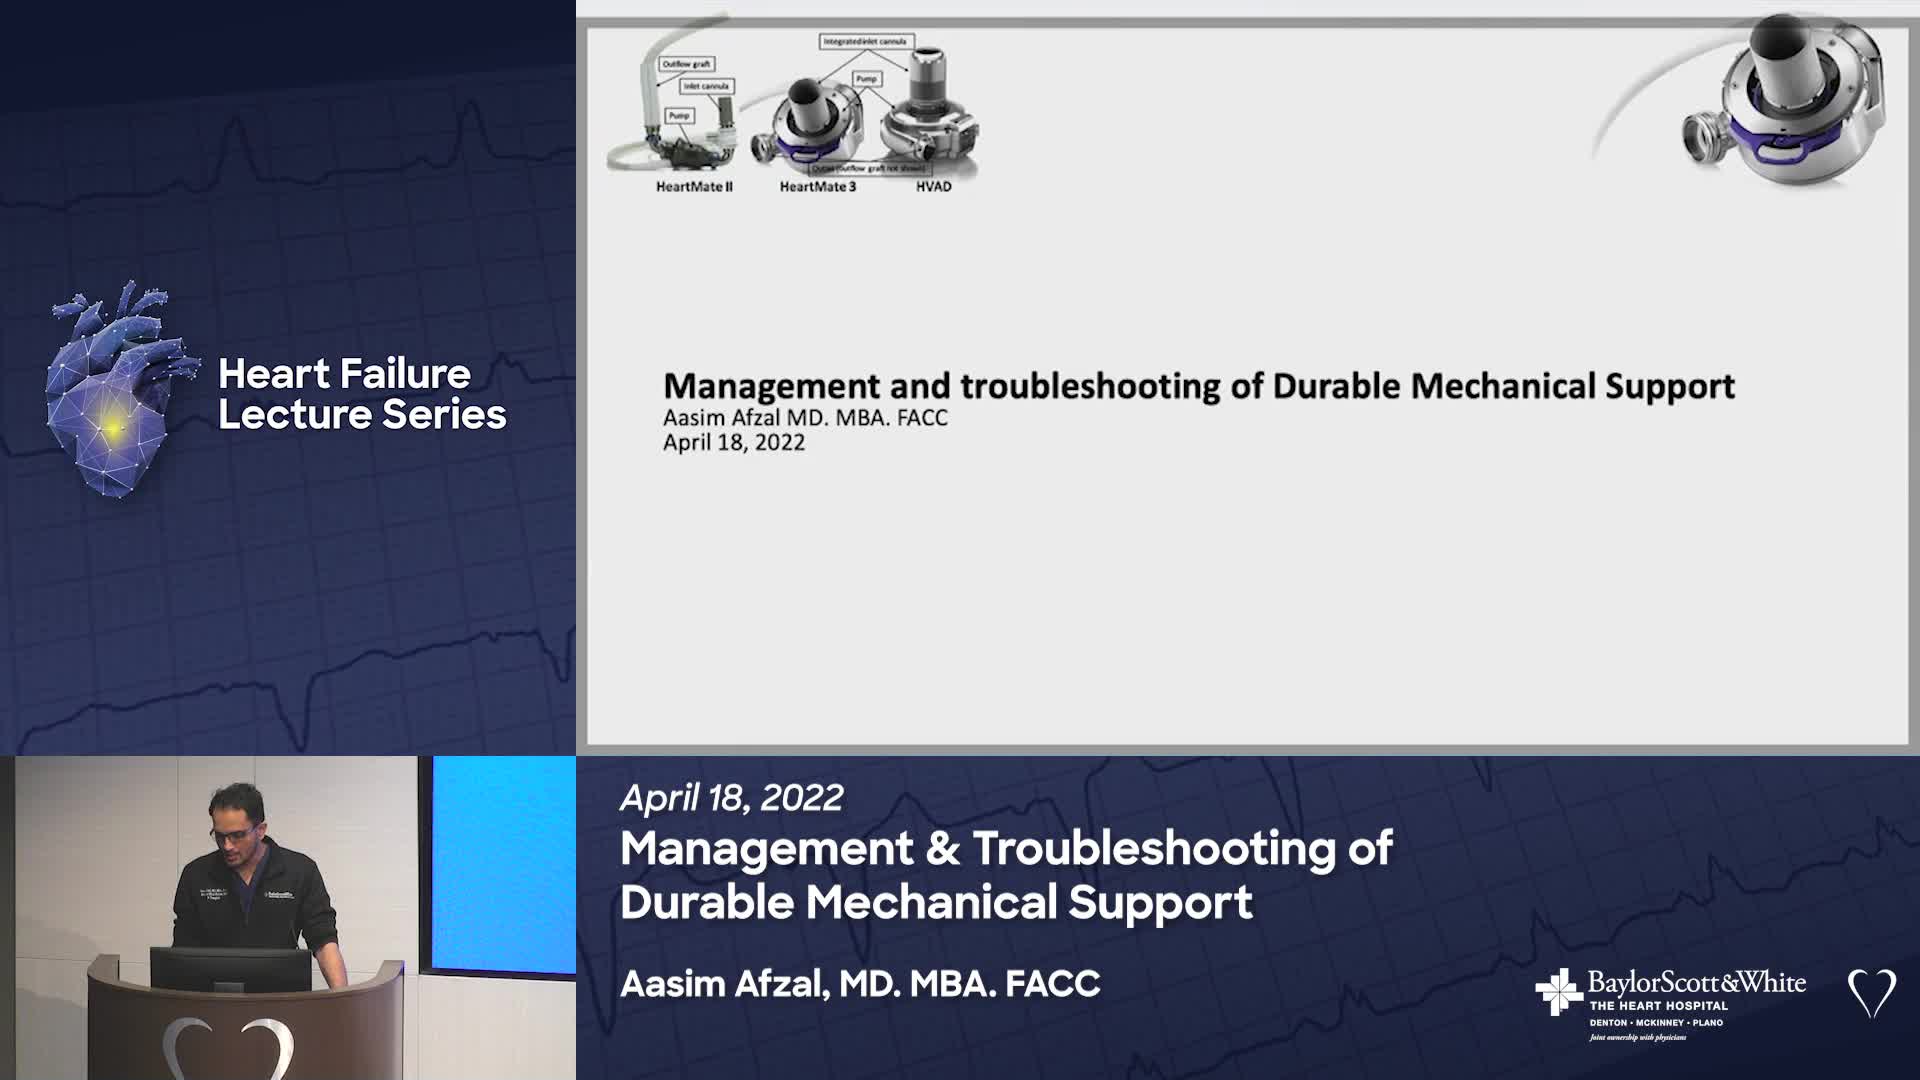

FACET

Our mission is to provide a collaborative environment and educational opportunities for physicians, scientists, nurses, and medical professionals to discuss and teach advanced techniques, improve clinical knowledge, and enhance the ability to provide excellent patient care, which ultimately improves patient health outcomes. To that end, the education program has strived to meet this goal educating and training the local, regional, and national medical community on the most recent advancements in medical science and research.

FACET CARDIOVASCULAR

FACET CARDIOVASCULAR